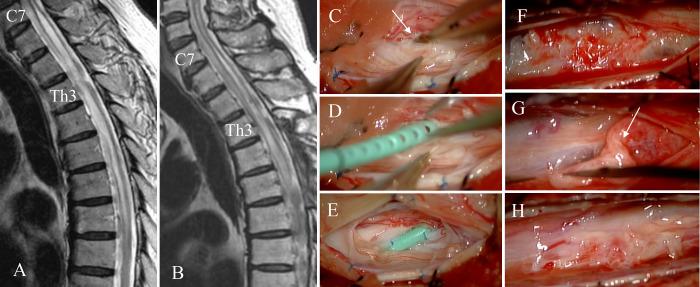

Spinal adhesive arachnoid pathology is a rare cause of myelopathy. Because of rarity and variability, mechanisms of myelopathy are unknown. The authors retrospectively analyzed patients to understand pathophysiology and provide implications for surgical treatment.

OBSERVATIONS

Nineteen consecutive patients were studied. Thirteen patients had a secondary pathology due to etiological disorders such as spinal surgery or hemorrhagic events. They received arachnoid lysis (4 patients), syringo-subarachnoid (S-S) shunt (8 patients) with or without lysis, or anterior decompression. Three of them developed motor deterioration after lysis, and 6 patients needed further 8 surgeries. Another 6 patients had idiopathic pathology showing dorsal arachnoid cyst formation at the thoracic level that was surgically resected. With mean follow-up of 44.3 months, only 4 patients with the secondary pathology showed improved neurological grade, whereas all patients with idiopathic pathology showed improvement.

LESSONS

The idiopathic pathology was the localized dorsal arachnoid adhesion that responded to surgical treatment. The secondary pathology produced disturbed venous circulation of the spinal cord by extensive adhesions. Lysis of the thickened fibrous membrane with preservation of thin arachnoid over the spinal veins may provide safe decompression. S-S shunt was effective if the syrinx extended to the level of normal subarachnoid space.

脊髓粘连性蛛网膜病变是脊髓病的罕见病因。由于其罕见性和变异性,脊髓病的发病机制尚不清楚。作者对患者进行回顾性分析,以了解其病理生理学并为手术治疗提供启示。

观察结果

对19例连续患者进行了研究。13例患者因脊髓手术或出血事件等病因性疾病存在继发性病变。他们接受了蛛网膜松解术(4例患者)、脊髓空洞-蛛网膜下腔(S-S)分流术(8例患者,伴或不伴松解术)或前路减压术。其中3例患者在松解术后出现运动功能恶化,6例患者需要进一步进行8次手术。另外6例患者患有特发性病变,表现为胸段背侧蛛网膜囊肿形成,均接受了手术切除。平均随访44.3个月,只有4例继发性病变患者的神经功能分级有所改善,而所有特发性病变患者均有改善。

经验教训

特发性病变为局限性背侧蛛网膜粘连,对手术治疗有反应。继发性病变通过广泛粘连导致脊髓静脉循环障碍。在保留脊髓静脉上方薄蛛网膜的情况下,松解增厚的纤维膜可提供安全的减压。如果脊髓空洞延伸至正常蛛网膜下腔水平,S-S分流术是有效的。